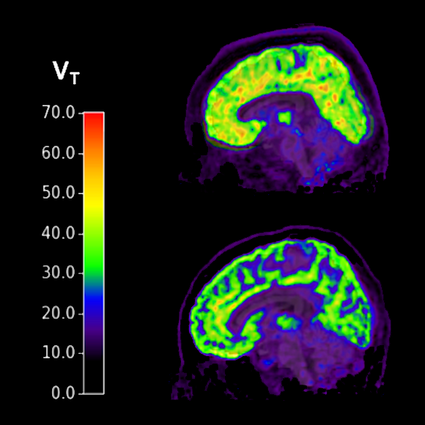

Brains of individuals with PTSD and suicidal thoughts (top) show higher levels of mGluR5 compared to healthy controls (bottom).

Researchers used PET imaging to measure levels of metabotropic glutamatergic receptor 5 (mGluR5) — which has been implicated in anxiety and mood disorders — in individuals with PTSD and major depressive disorder. They found high levels of mGluR5 in the PTSD group with current suicidal thoughts. They found no such elevated levels in the PTSD group with no suicidal thoughts or in those with depression, with or without current suicidal thoughts.